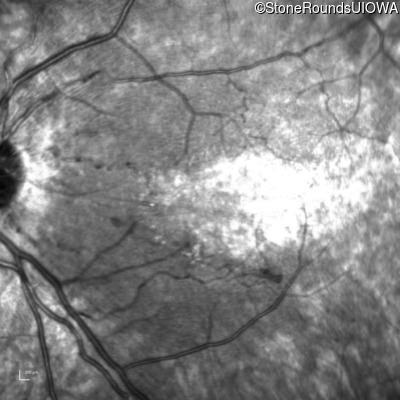

Infrared Fundus Photograph - Left - 20/80 -1

Exemplar